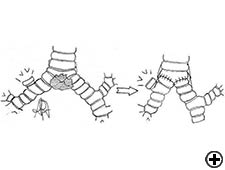

In isolated carinal resection and reconstruction, applicable for centrally located, low grade and small tumors (Video 8), the right and left main bronchi can be medially sutured to create a new carina, that is subsequently anastomosed to the distal trachea (Figure 2C and Video 9). A less common technique provides the resection of the carina followed by an end-to-end anastomosis between the left main bronchus and the trachea, followed by anastomosis of the right main bronchus to the lateral, cartilaginous wall of the trachea, paying attention to stay at least 2 cm above the first anastomosis (Figure 6). When more advanced tracheal involvement is present, two alternative techniques may be used to avoid excessive tension: an end-to-end anastomosis between the right main bronchus and the trachea, followed by anastomosis of the left main bronchus to the lateral, cartilaginous wall of the bronchus intermedius or an end-to-end anastomosis between the left main bronchus and the trachea, followed by anastomosis of the right main bronchus to the lateral, cartilaginous wall of the left main bronchus (Figure 7). In all of cases a wide hilar release is mandatory to reduce tension on the anastomoses.

Tracheal sleeve lobectomy is a challenging operation usually required for management of neoplasms involving the trachea or the carina and the proximal right main bronchus extending to the origin of the right upper bronchus (Figure 8). In cases of contraindication for sleeve pneumonectomy or in case of low-grade neoplasm, the carina, right main bronchus, and right upper lobe may be removed. The reconstruction consists of an end-to-end anastomosis of the left main bronchus to the trachea, and creation of a secondary end-to-side anastomosis of the bronchus intermedius either to the trachea (Figure 9) or more frequently to the left main bronchus (Figure 10), because elevating the bronchus intermedius to the side of the trachea often creates excessive tension, with high risk of fistula or stenosis.